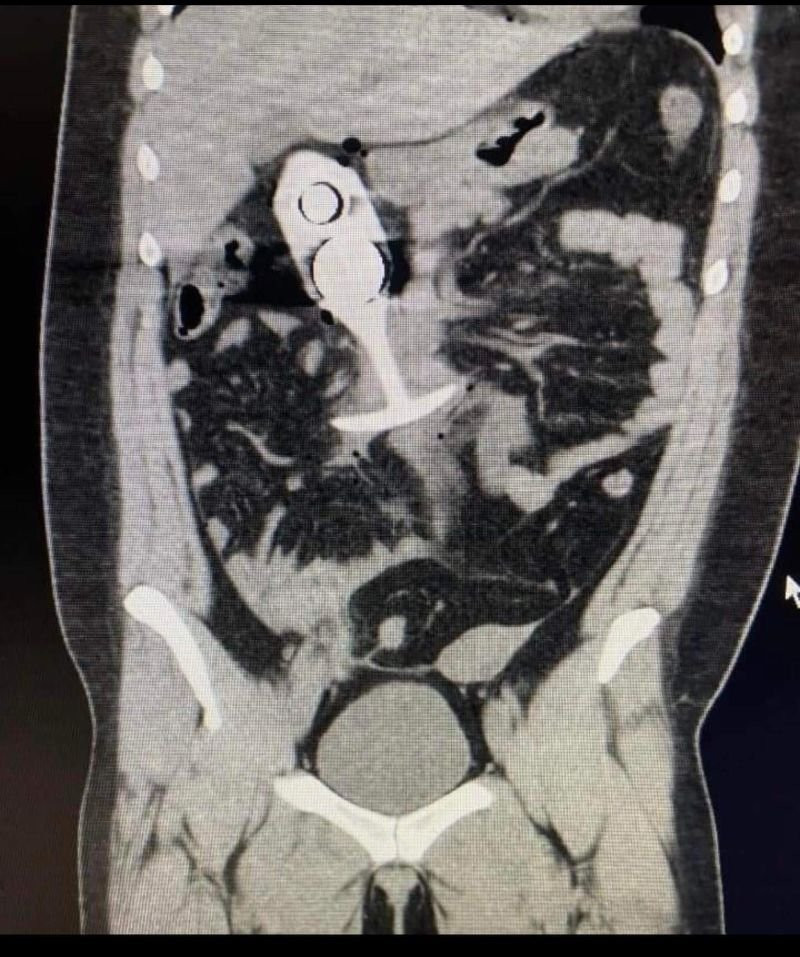

Стоит сказать, что этот инцидент произошел еще в апреле. Подробности о травмах неизвестны. В мае в Сети появились снимки, на котором хорошо видно секс-игрушку с двумя шариками. Сообщается, что рентгеновский снимок принадлежит именно пострадавшей.